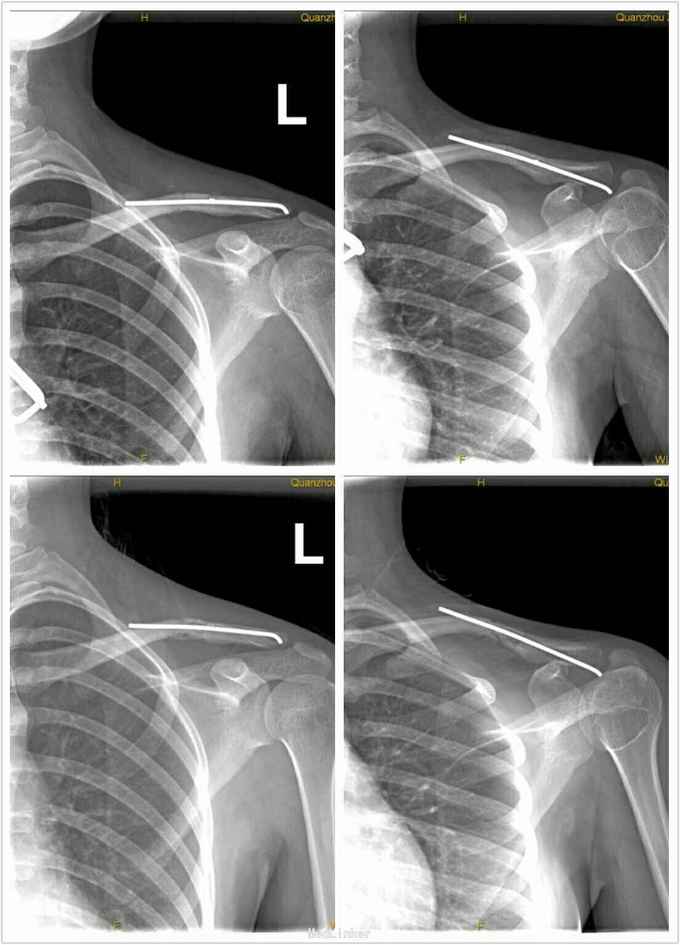

患者女,21岁,以“摔伤致左肩部肿痛、活动受限1小时”为主诉入院。 病史:患者于入院1小时前不慎摔伤,导致左肩部疼痛,并逐渐肿胀,左肩关节活动受限,伤后急诊我院。

查体:左肩部肿胀,未见出血及张力性水泡,无“方肩”畸形,左锁骨部压痛明显,可及骨擦感及异常活动,左肩锁关节处无压痛,无弹键感;左肩关节活动受限,左桡动脉搏动正常,左手各指活动正常,肢端感觉、血运均正常。余肢体关节未见明显异常。 辅助检查:X线片示:左锁骨中外段骨皮质中段,见锐利线影贯穿骨折,断端向上成角,远折节向内下方移位,与近端相重叠,肩关节关系未见明显异常;双肺纹理清晰,未见明显异常密度影,双肺门不大,纵膈不宽,心影大小形态正常,双膈面光整、肋膈角锐利。

诊断: 左锁骨中外1/3骨折。 治疗:急诊在麻醉下行“左锁骨骨折闭合复位经皮克氏针内固定术”。